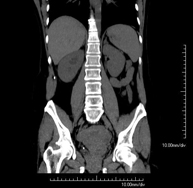

- Abdominal and pelvic CT

Diagnostic test that consists of obtaining high-definition anatomical images (bone structures, vascular structures, liver, pancreas, gallbladder, kidneys, adrenal glands, spleen, small and large intestine, bladder, uterus and ovaries, prostate and seminal vesicles, ureters, etc.) using CT (computed tomography) equipment. Most studies require the use of iodinated contrast.